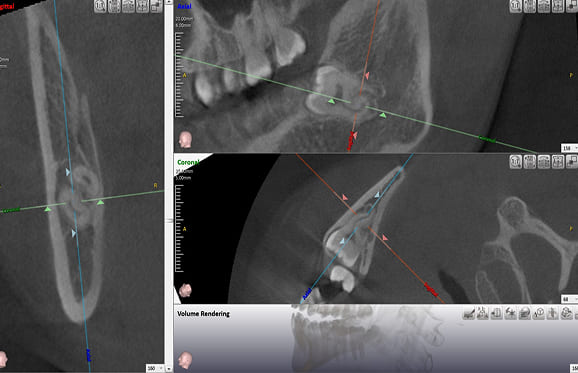

● 上の顎の奥歯にインプラントを入れるのに骨が足りないため、ソケットリフトと人工骨補填して骨造成を行った症例1

術前

藤沢デンタルオフィスのインプラント術前 藤沢デンタルオフィスのインプラント術前

3Dシミュレーション

術後

藤沢デンタルオフィスのインプラント術後 藤沢デンタルオフィスのインプラント術後

シミュレーション通りの上顎洞底挙上と人工骨補填(3Dガイドシステム使用)

● 上の顎の奥歯にインプラントを入れるのに骨が足りないため、ソケットリフトと人工骨補填して骨造成を行った症例2